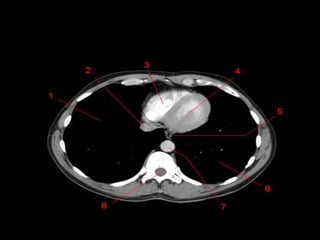

• 1: vasos braquiocefálicos

direitos.

• 2: aorta ascendente e veia

cava superior superpostas.

• 3: átrio direito.

• 4: veia cava inferior.

• 5: vasos braquiocefálicos

esquerdos.

• 6: arco aórtico.

• 7: tronco pulmonar.

• 8: apêndice atrial

esquerdo.

• 9: ventrículo esquerdo

Mediastino • 1: vasosbraquiocefálicos direitos. • 2: aorta ascendente e veia cava superior superpostas. • 3: átrio direito. • 4: veia cava inferior. • 5: vasos braquiocefálicos esquerdos. • 6: arco aórtico. • 7: tronco pulmonar. • 8: apêndice atrial esquerdo. • 9: ventrículo esquerdo